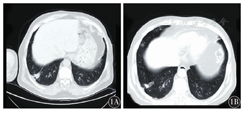

患者,男性,62岁,2018年2月1日因咳嗽伴牙龈出血2周入院。血常规示:血红蛋白61 g/L,红细胞计数1.83×1012/L,白细胞计数3.32×109/L,中性粒细胞0.286,淋巴细胞0.322,单核细胞0.392,血小板计数11×109/L。外周血涂片见大量幼稚细胞,肝肾功能未见明显异常。2018年2月3日胸部CT示:右下肺小结节及左肺舌段、右中肺炎症(图1)。骨髓穿刺病理示APL(图2)。骨髓免疫分型:骨髓中异常细胞占91.5%,异常细胞表达CD9、CD13、CD33、CD38、CD64、CD117、CD123、MPO,部分表达CD15,BCR1型PML-RARα融合基因阳性,拷贝数为74 256。初步诊断为:急性髓系白血病(AML)M3型,美国东部肿瘤协作组(ECOG)评分0分。予以对症治疗改善症状,予维甲酸20 mg口服,2次/d,2个诱导疗程后复查骨髓细胞提示完全缓解。继续予以抗感染治疗,多次复查CT均示肺部感染较前吸收,右下肺结节性质待定,建议行肺穿刺活组织检查,患者家属拒绝,复查多次胸部CT均未见右下肺结节明显进展,感染灶较前吸收(图1),考虑右下肺结节为感染灶可能性较大。2018年4月11日给予伊达比星10 mg第1天至第3天,复查骨髓示PML-RARα融合基因阴性。2018年6月5日再给予三氧化二砷10 mg第1天至第14天治疗。再次复查胸部CT示:两肺感染,右中肺及右下肺高密度影,考虑炎症可能性大,右中肺可疑小结节。骨髓穿刺结果示:骨髓增生活跃,细胞形态未见明显异常,考虑为AML-M3完全缓解,且肺部结节病灶未见明显增长,故未再进行活组织检查。